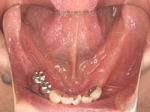

両側5歯症例

両側5歯症例両側5歯症例両側5歯症例 主訴-義歯のバネが壊れて手前の歯が痛んできた。 術前(旧義歯装着、鏡像) 術前(下顎粘膜面、鏡像)術前(下顎粘膜面、鏡像)術前(下顎粘膜面、鏡像) 術前レントゲン術前レントゲン術前レントゲン 術前口腔内(正面観)術前口腔内(正面観)術前口腔内(正面観)

術後(鏡像)術後(鏡像)術後(鏡像) 術後口腔内(正面観)術後口腔内(正面観)術後口腔内(正面観)もう入れ歯は要らなくなりました。 術後レントゲン術後レントゲン術後レントゲン